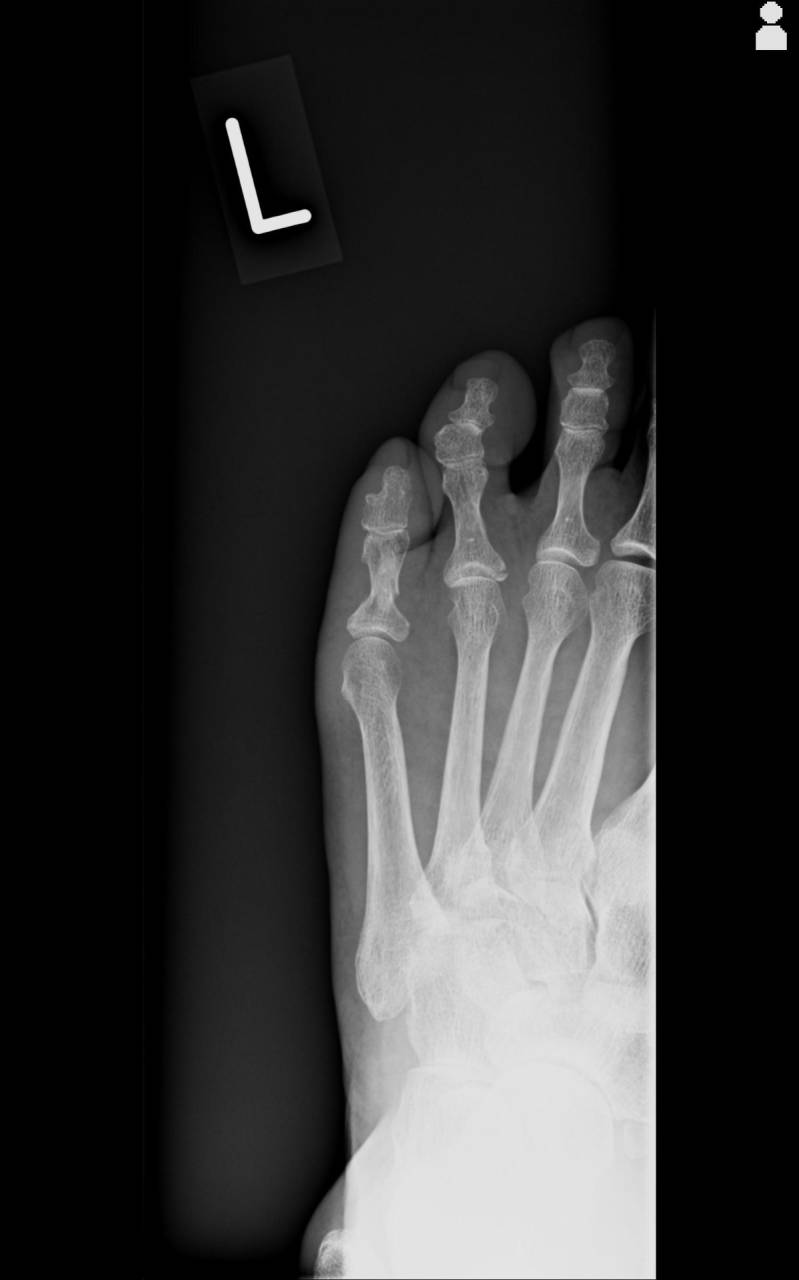

当整骨院が提携している病院にてレントゲン検査を依頼し、撮影した画像を確認すると左第5趾基節骨骨幹部骨折と左第4趾基節骨基部骨折があり、骨折として施術を進めていきます。

施術は左第5趾の骨折部の変形があったため整復を行い、その後キャスト(ギプス)にて牽引固定を行いました。